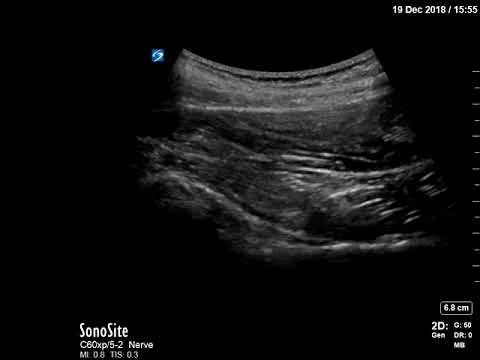

Knee effusion

Small left knee effusion